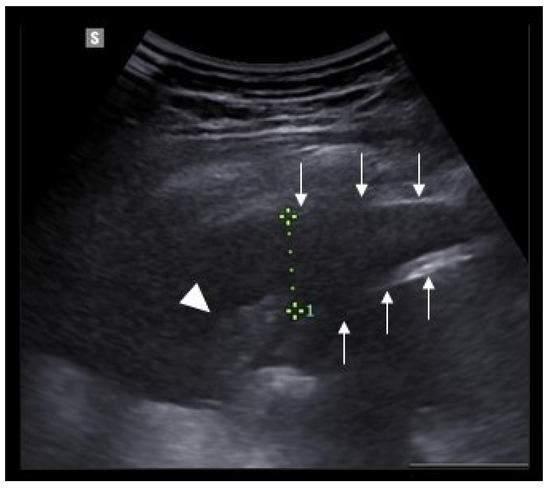

- Musolino, A.M.; Tomà, P.; Supino, M.C.; Scialanga, B.; Mesturino, A.; Scateni, S.; Battaglia, M.; Pirozzi, N.; Bock, C.; Buonsenso, D. Lung ultrasound features of children with complicated and noncomplicated community acquired pneumonia: A prospective study. Pediatr. Pulmonol. 2019, 54, 1479–1486. [Google Scholar] [CrossRef] [PubMed]

- Deganello, A.; Rafailidis, V.; Sellars, M.E.; Ntoulia, A.; Kalogerakou, K.; Ruiz, G.; Cosgrove, D.O.; Sidhu, P.S. Intravenous and Intracavitary Use of Contrast-Enhanced Ultrasound in the Evaluation and Management of Complicated Pediatric Pneumonia. J. Ultrasound Med. 2017, 36, 1943–1954. [Google Scholar] [CrossRef] [PubMed]